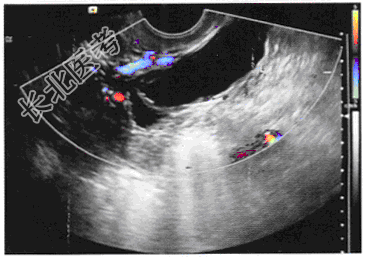

- 单项选择题女,27岁, 下腹部疼痛数月。体检:右侧附件区增厚、增大, B超检查如图所示,以下最可能的诊断为

A、右侧输卵管积液

B、右侧卵巢肿瘤

C、右侧卵巢囊肿

D、盆腔积液

E、右侧输尿管扩张